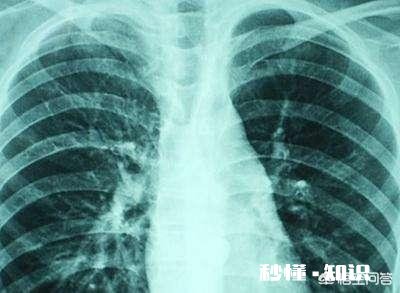

文章插图